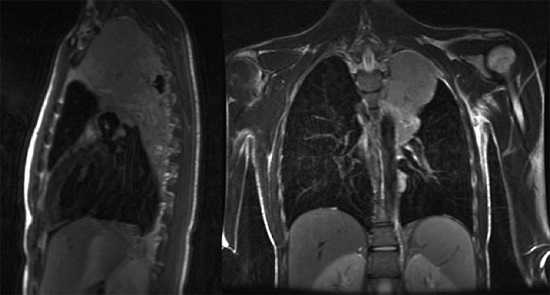

Что показывает МРТ органов грудной клетки

В грудной клетке расположено множество жизненно важных органов, патологии которых сложно диагностировать классическими способами: они скрыты за костями грудины, ребрами, позвоночником, мягкими тканями. Информативным способом, который способен показать структуру, а также функциональность органов, расположенных здесь, врачи называют МРТ — магнитно-резонансную томографию с контрастом или без него. Метод идеально подходит для исследования находящихся внутри грудины органов, сосудов, желез, лимфоузлов, но наиболее эффективным его считают в диагностике опухолевых процессов.

Магнитно-ядерная томография не очень информативна при исследовании костных тканей. Плохо видны на снимках и легкие, в которых слишком много воздуха. В процессе дыхания они двигаются, что не позволяет получить четкие изображения легочных тканей. Чтобы повысить четкость картинки, врач может попросить пациента во время сканирования периодически задерживать дыхание на вдохе. Та же проблема наблюдается при попытке проверить сердечную мышцу — ее ритмичные сокращения мешают обследовать миокард на патологии. Однако временно остановить сердце невозможно, поэтому оно фактически является единственным органом в груди, который проверяют с помощью так называемой синхронизации с пульсом/ЭКГ.